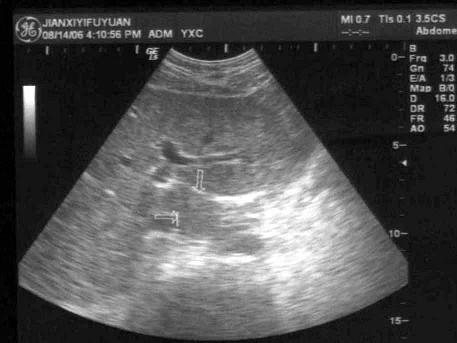

问题 肋缘下斜切面显示门静脉左支时,可见肝尾叶位于?(?)

选项 A.门静脉左支矢状段与胆囊之间 B.门静脉左支横段与下腔静脉之间 C.肝右静脉与胆囊之间 D.肝门静脉与肝静脉之间 E.以上都不是

答案 B